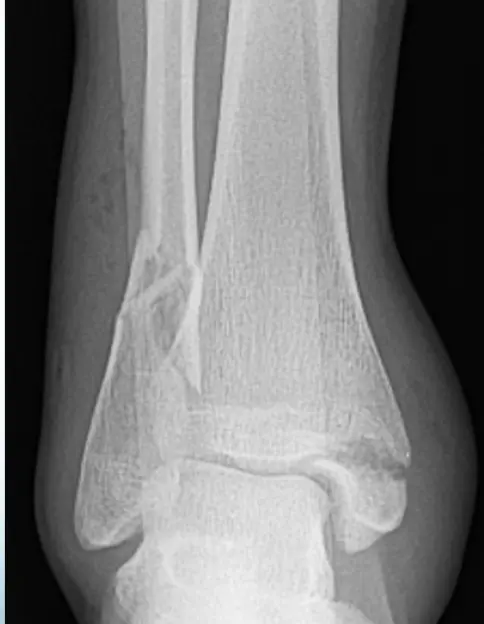

Patient: 32âyearâold male with a severe twisting ankle injury â painful, swollen and unable to stand.

Findings

- Site: lateral malleolus

- Fracture type: simple

- Fracture line: spiral

- Displacement: gap medially

- Special issue: possible ruptured deltoid ligament